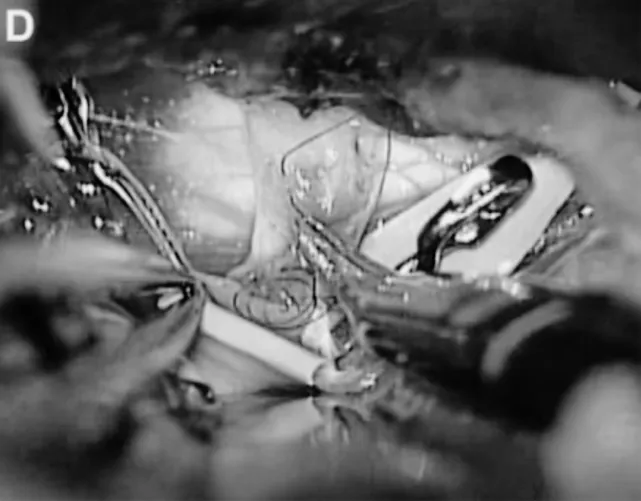

医生通过左侧颞下入路,选择后颞动脉作为受体(图C、D),成功完成搭桥和孤立术,整个手术过程如同在“万丈悬崖边绣花”,每一步都要求精准到毫米,既要避免损伤周围神经和血管,又要保证吻合口毫无渗漏。

C、D.选择颞后动脉(箭头标注)作为受体动脉,经左侧颞下入路用连续缝合行颞浅动脉-颞后动脉吻合;